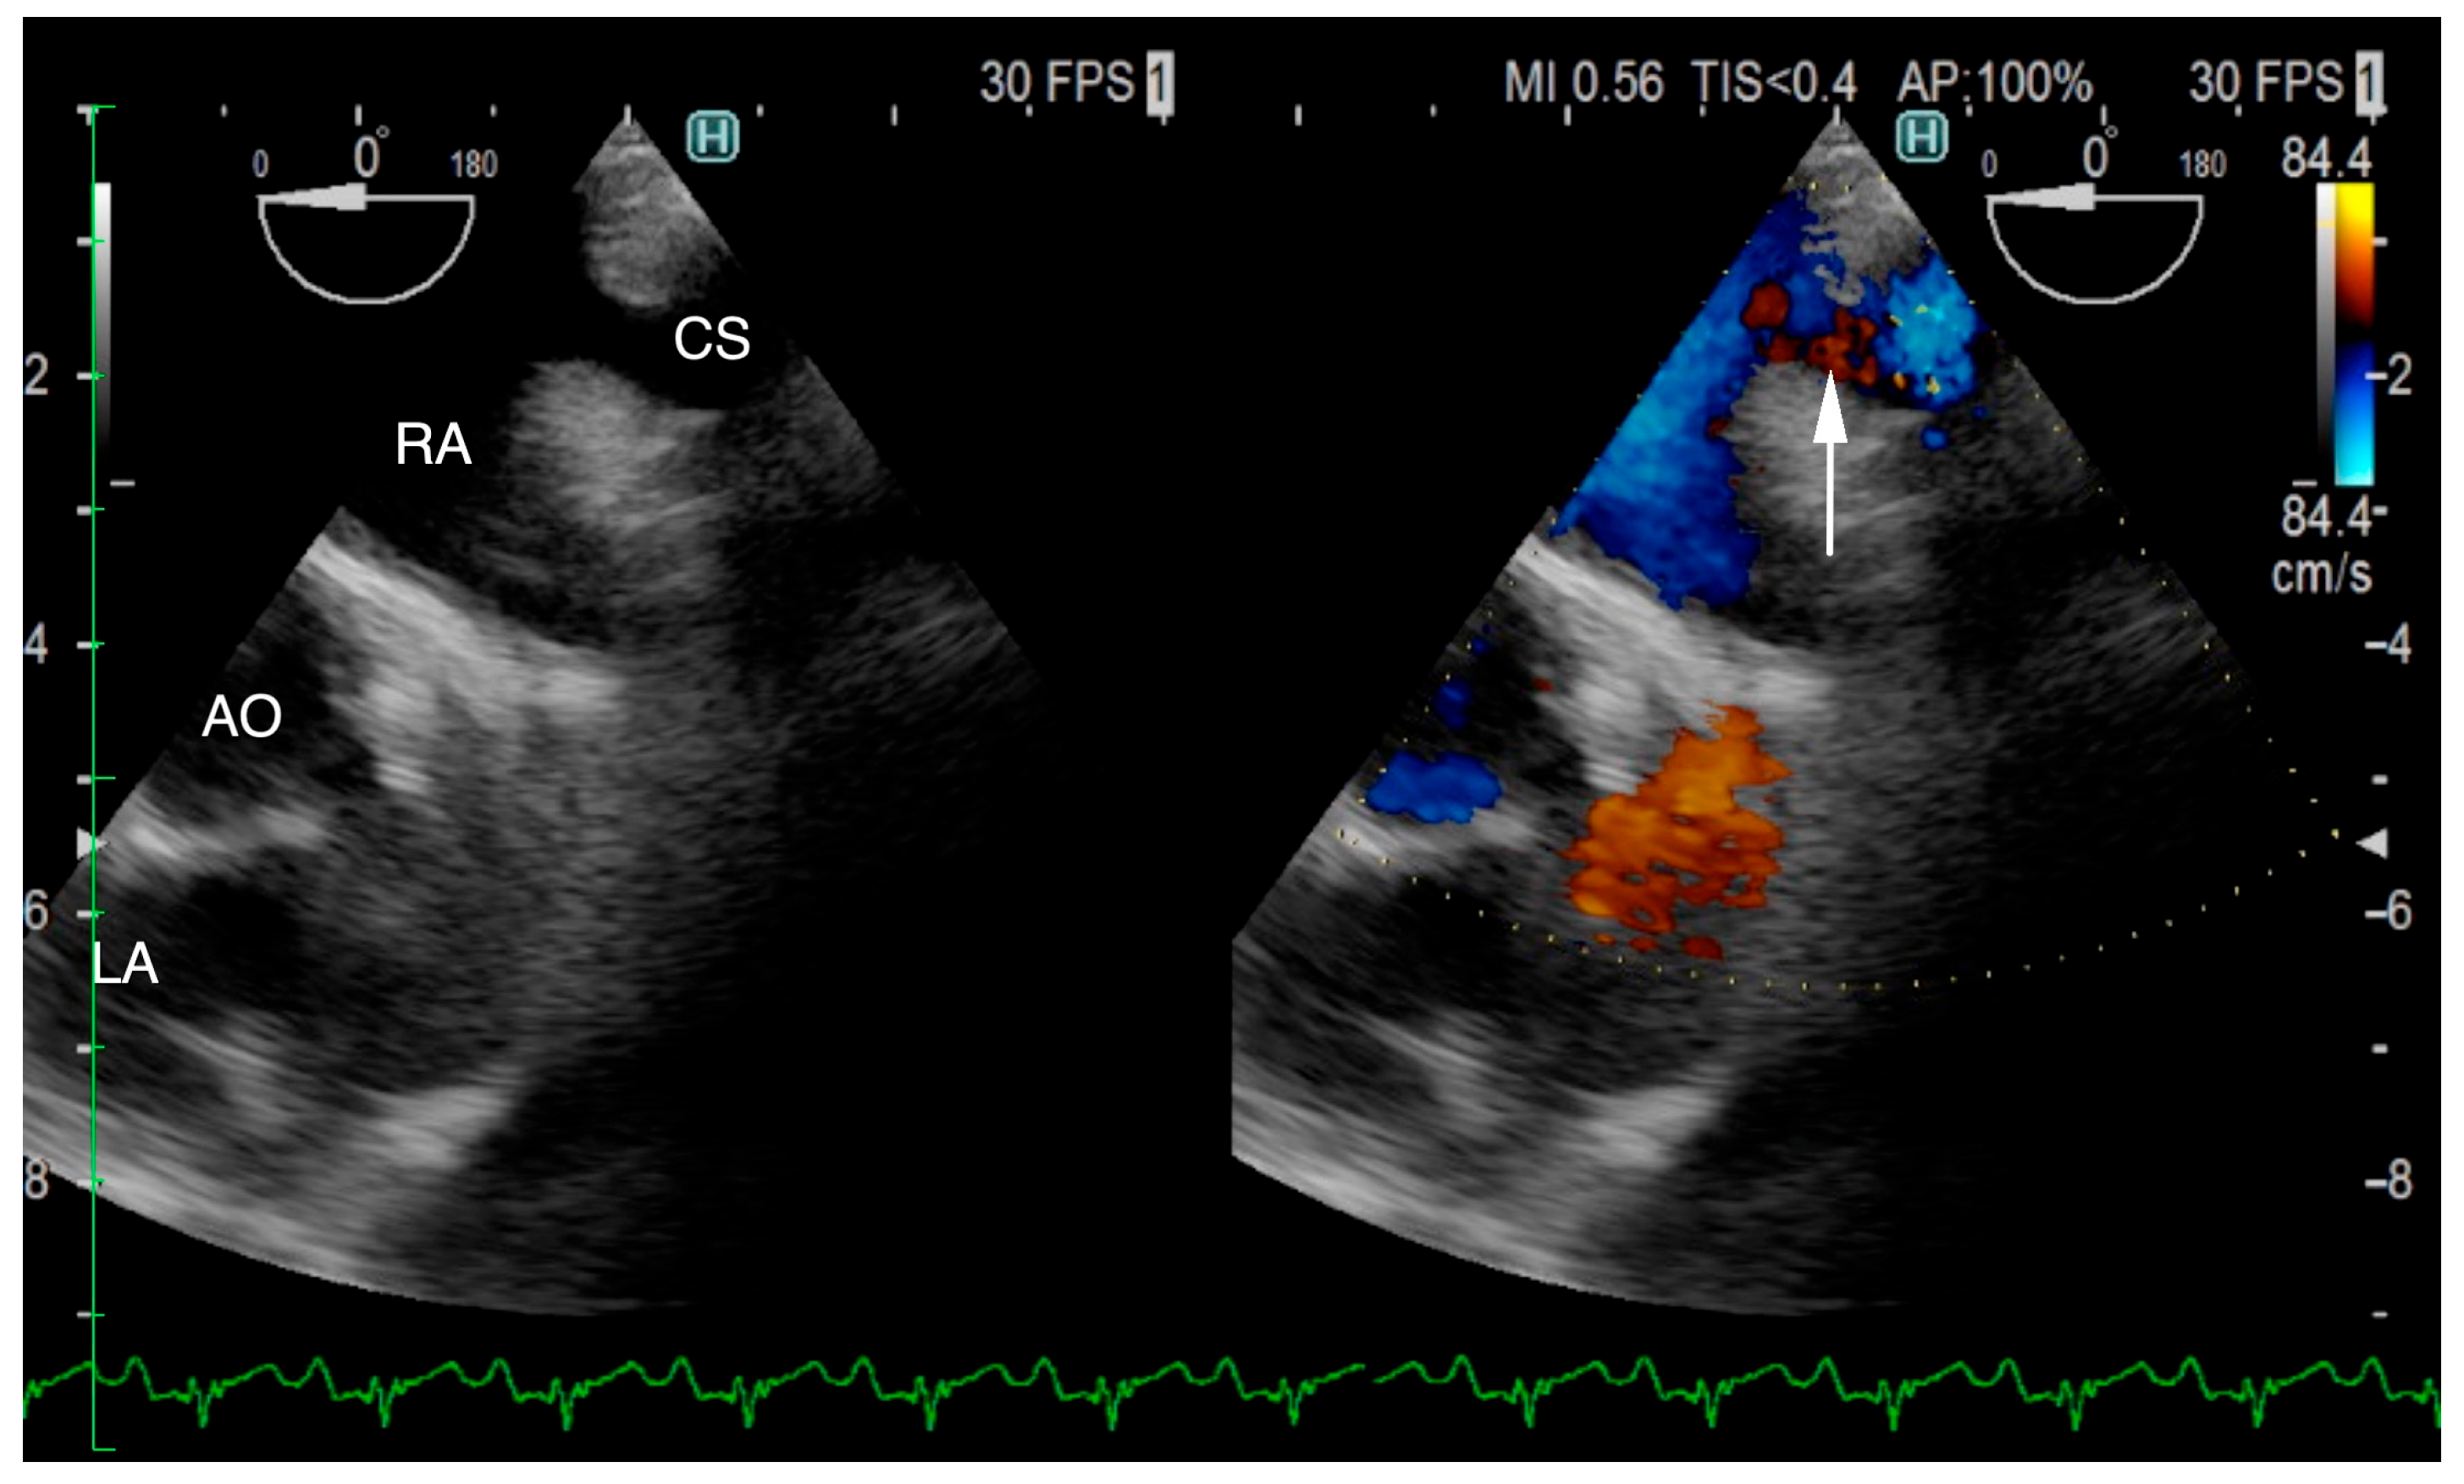

The ECG-gated CT showed communication between the LA and RA via the CS (Figure 2a). An enlargement of the CS, where the coronary artery measured 0.8 mm in diameter, whereas the CS measured 11.6 mm, was observed (Figure 2b). The CS drained normally into the RA; however, an ostium to the LA was seen, leading to the diagnosis of UCSS (Figure 3a). Under general anesthesia, TEE was also conducted using LISSENDO 880LE (Fujifilm Ltd., Tokyo, Japan) equipped with the 8–2 MHz phase array transesophageal probe (Fujifilm Ltd., Tokyo, Japan). With TEE, it was possible to identify the shunt as an abnormally large CS running along the cardiac wall (Figure 4).

When diagnosing UCSS, using just TTE may leave a risk of misdiagnosis [16]. In our case, the CS volume was overloaded. Considering that the mean diameter of the CS ostium in dogs is 5.5 ± 1.3 mm, the coronary sinus had become severely enlarged [17]. ECG-gated CT images showed that the diameter of the CS was 14.5 times larger than that of the coronary artery (Figure 2b). The largeness of the CS led to its appearance during the TTE as an irregular blood flow communicating between the LA to the RA, thus supporting the initial misdiagnosis of ASD. It is important to consider the possibility of extracardiac blood flow when no intracardiac defect is identifiable.

Figure 2. (a) ECG-gated CT multiplanar reconstruction (left oblique sagittal view) demonstrating the irregular communication between the RA and LA (arrow) that is formed by the unroofed CS. The opening in the CS allows blood flow from the RA to the LA. (b) ECG-gated CT volume rendering (sagittal slice, left lateral view, observed from the right) showing the markedly enlarged CS (red arrow) compared to the CA (yellow arrow). The CS measures 11.6 mm in diameter and is abnormally large compared to the CA, measuring 0.8 mm. CS, coronary sinus; CA, coronary artery LA, left atrium; LV, left ventricle; RA, right atrium; RV, right ventricle; SVC, superior vena cava.